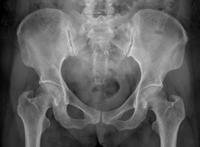

女性骨盆x光照片